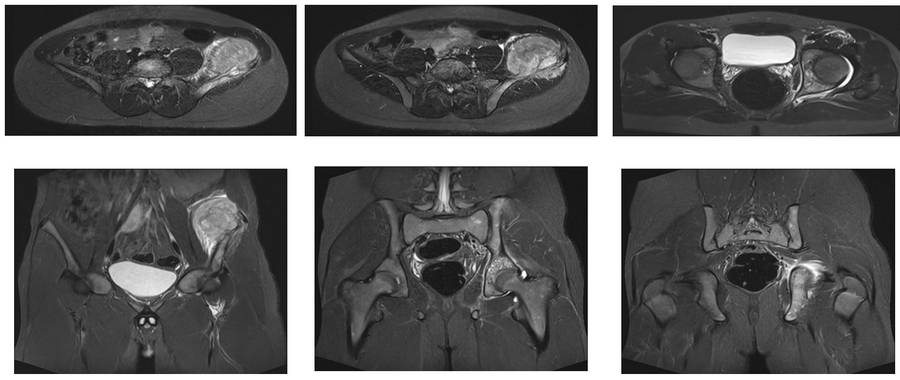

Before the surgery: The MRI shows tumor tissue accompanied by a soft tissue mass involving the entire left iliac crest.